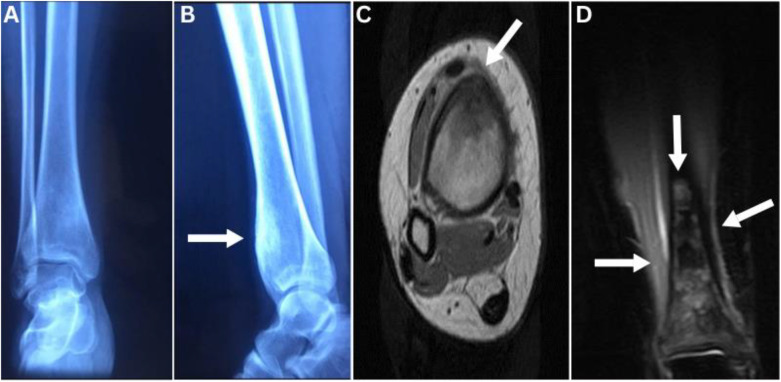

Osteoid osteomas (OO) are benign neoplasms commonly present during the second and third decade of life, showing a male predominance with classical nocturnal bone pain dramatically responding to nonsteroidal anti-inflammatory drugs. We report a 22-year-old female patient who presented at a teaching hospital, Baghdad, Iraq, in 2023. She presented with right leg bone pain that was exacerbated during menstruation, a presentation that had never been reported in the literature before. The pain intensity increased and interfered with her daily activity. A computed tomography scan showed OO signs and surgical excision and histopathology confirmed OO. The patient's pain reduced to 0 on the visual analog scale. She has no recurrence signs 2 years after the surgery. This novel OO presentation may increase physician awareness of atypical presentation. A careful evaluation of a challenging presentation added to an imaging study may reveal the underlying cause and exclude other diagnostic dilemmas.